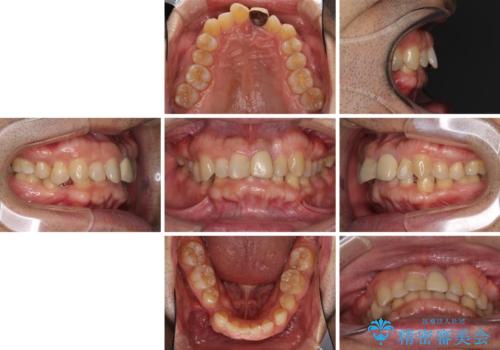

- 上下前歯のデコボコと下顎小臼歯の欠損によるスペースを気にして来院された患者様です。

下顎は左右1本ずつ小臼歯が欠損しており、右側にはやや大きな欠損がありました。

欠損により下顎歯列は相対的に小さく、上顎に深く咬みこんでしまうディープバイトとなっていました。

インビザラインによる治療を希望されたため、左側のスペースは閉じ、右側はスペースをより拡大し、インプラント補綴を行うこととしました。

咬合力が強く、インビザラインのみではディープバイトを改善することができず、半年間ほどワイヤー装置による矯正治療を行いました。

インプラントの埋入は矯正治療中に行い、矯正治療後はインプラント上補綴および、前歯のセラミック治療を行いました。